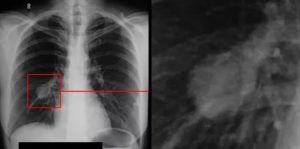

Расшифровкой рентгенофотографии занимается рентгенолог. При этом учитывается характер затемнения в лёгочной ткани, выделить можно следующие показатели:

- Сегментарные пятна — затемнение в форме треугольника, обрамленное светлым контуром. Единичное проявление говорит о травмировании лёгочной ткани, присутствии в области органа инородного предмета или эндобронхиальной опухоли. Если треугольников 2 и более, это может быть пневмония, онкология, жидкость в плевральной области, туберкулёз или распространение метастазов.

- Долевое пятно, очерченное чётким контуром — лёгочное заболевание, например, гнойное воспаление, бронхоэктазия и прочие.

- Очаговое затемнение или пятно размером до 10 миллиметров указывает на патологии сердца и сосудов, онкологическое новообразование. Очаговое пятно характерно для инфаркта миокарда, но для уточнения диагноза требуется проведение МРТ.

- Сфокусированные пятна на поверхности органа свидетельствуют о разных типах воспаления лёгких, развитии бронхиальной астмы, гнойных воспалениях в лёгких, глистных инвазиях или скоплении плеврального выпота.

Трактовка происходит по-разному, поэтому расшифровкой должен заниматься опытный рентгенолог. Важно знать, что здоровые лёгкие на снимки имеют равномерный цвет, а сердце и бронхи выглядят светлыми.